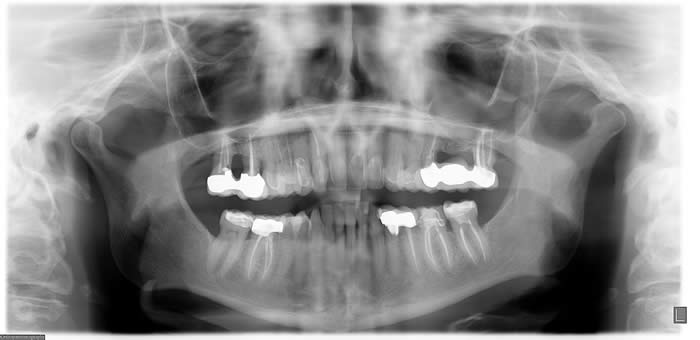

A screening image, typically a panoramic radiograph, permits assessment of the form of the condyle and the integrity of the cortex and is an important adjunct to the initial history and examination. An additional benefit of a panoramic image is the ability to visualize other structures in the maxillofacial region. In a panoramic image the condyles are intentionally brought down and forward in the fossae by having the patient protrude the mandible, but the condyles may still be partially obscured by adjacent bony structures.

With the advent of cone beam CT (CBCT) imaging, it is now possible to acquire a panoramic image with the teeth together, thus making it possible to see the condyles in their relationship to their fossae.

Because conventional panoramic imaging is still more common still more commonly available in dental offices than is CBCT, and because a conventional panoramic exposes the patient to less radiation than a CBCT scan, the conventional panoramic is the preferred choice as a screening image for most TMD patients.